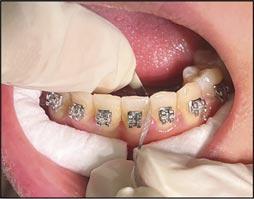

Research advocates for an improvement in gingival health when flossing is incorporated into oral hygiene routines (Figure 4).11 Zannata et al. found that there are small but statistically significant benefits to using dental floss in FA patients.1 In contrast to this, other studies have found insufficient evidence that routine instruction in floss use should be provided to all patients.12

Interdental brushes

IDBs are reported to be the most effective method of cleaning interproximal surfaces (Figures 5a, 5b and 5c). The evidence suggests superior plaque removal when compared to both toothbrushing alone and toothbrushing combined with floss.13 The added benefit is their ease of use in the presence of FAs, allowing for cleaning around

appliances, and therefore increasing compliance. IDBs as adjuncts to toothbrushing are recommended by several authors given their ability to more effectively remove plaque than brushing alone.14